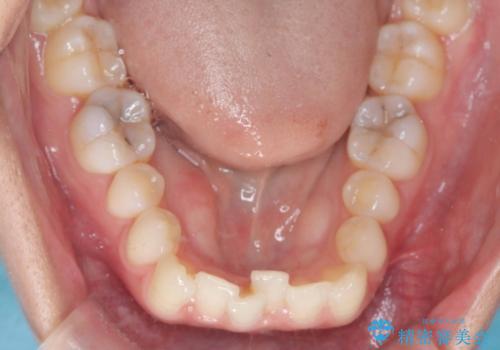

- 歯のデコボコ(叢生)を主訴にご来院された患者様です。

精密矯正検査を行った結果、歯を抜かずに行う、非抜歯のワイヤー矯正で治療を行う方針となりました。

歯並びの乱れに加え、**反対咬合(上下のかみ合わせのズレ)**も認められたため、見た目だけでなく、かみ合わせの改善も同時に行っています。